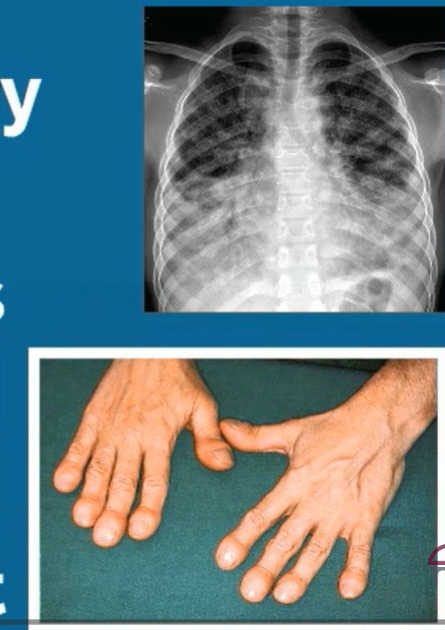

- 손톱 끝이 둥글게 부풀어 오르는 곤봉지

✔ 흉부 CT에서 이상 소견이 나온 경우